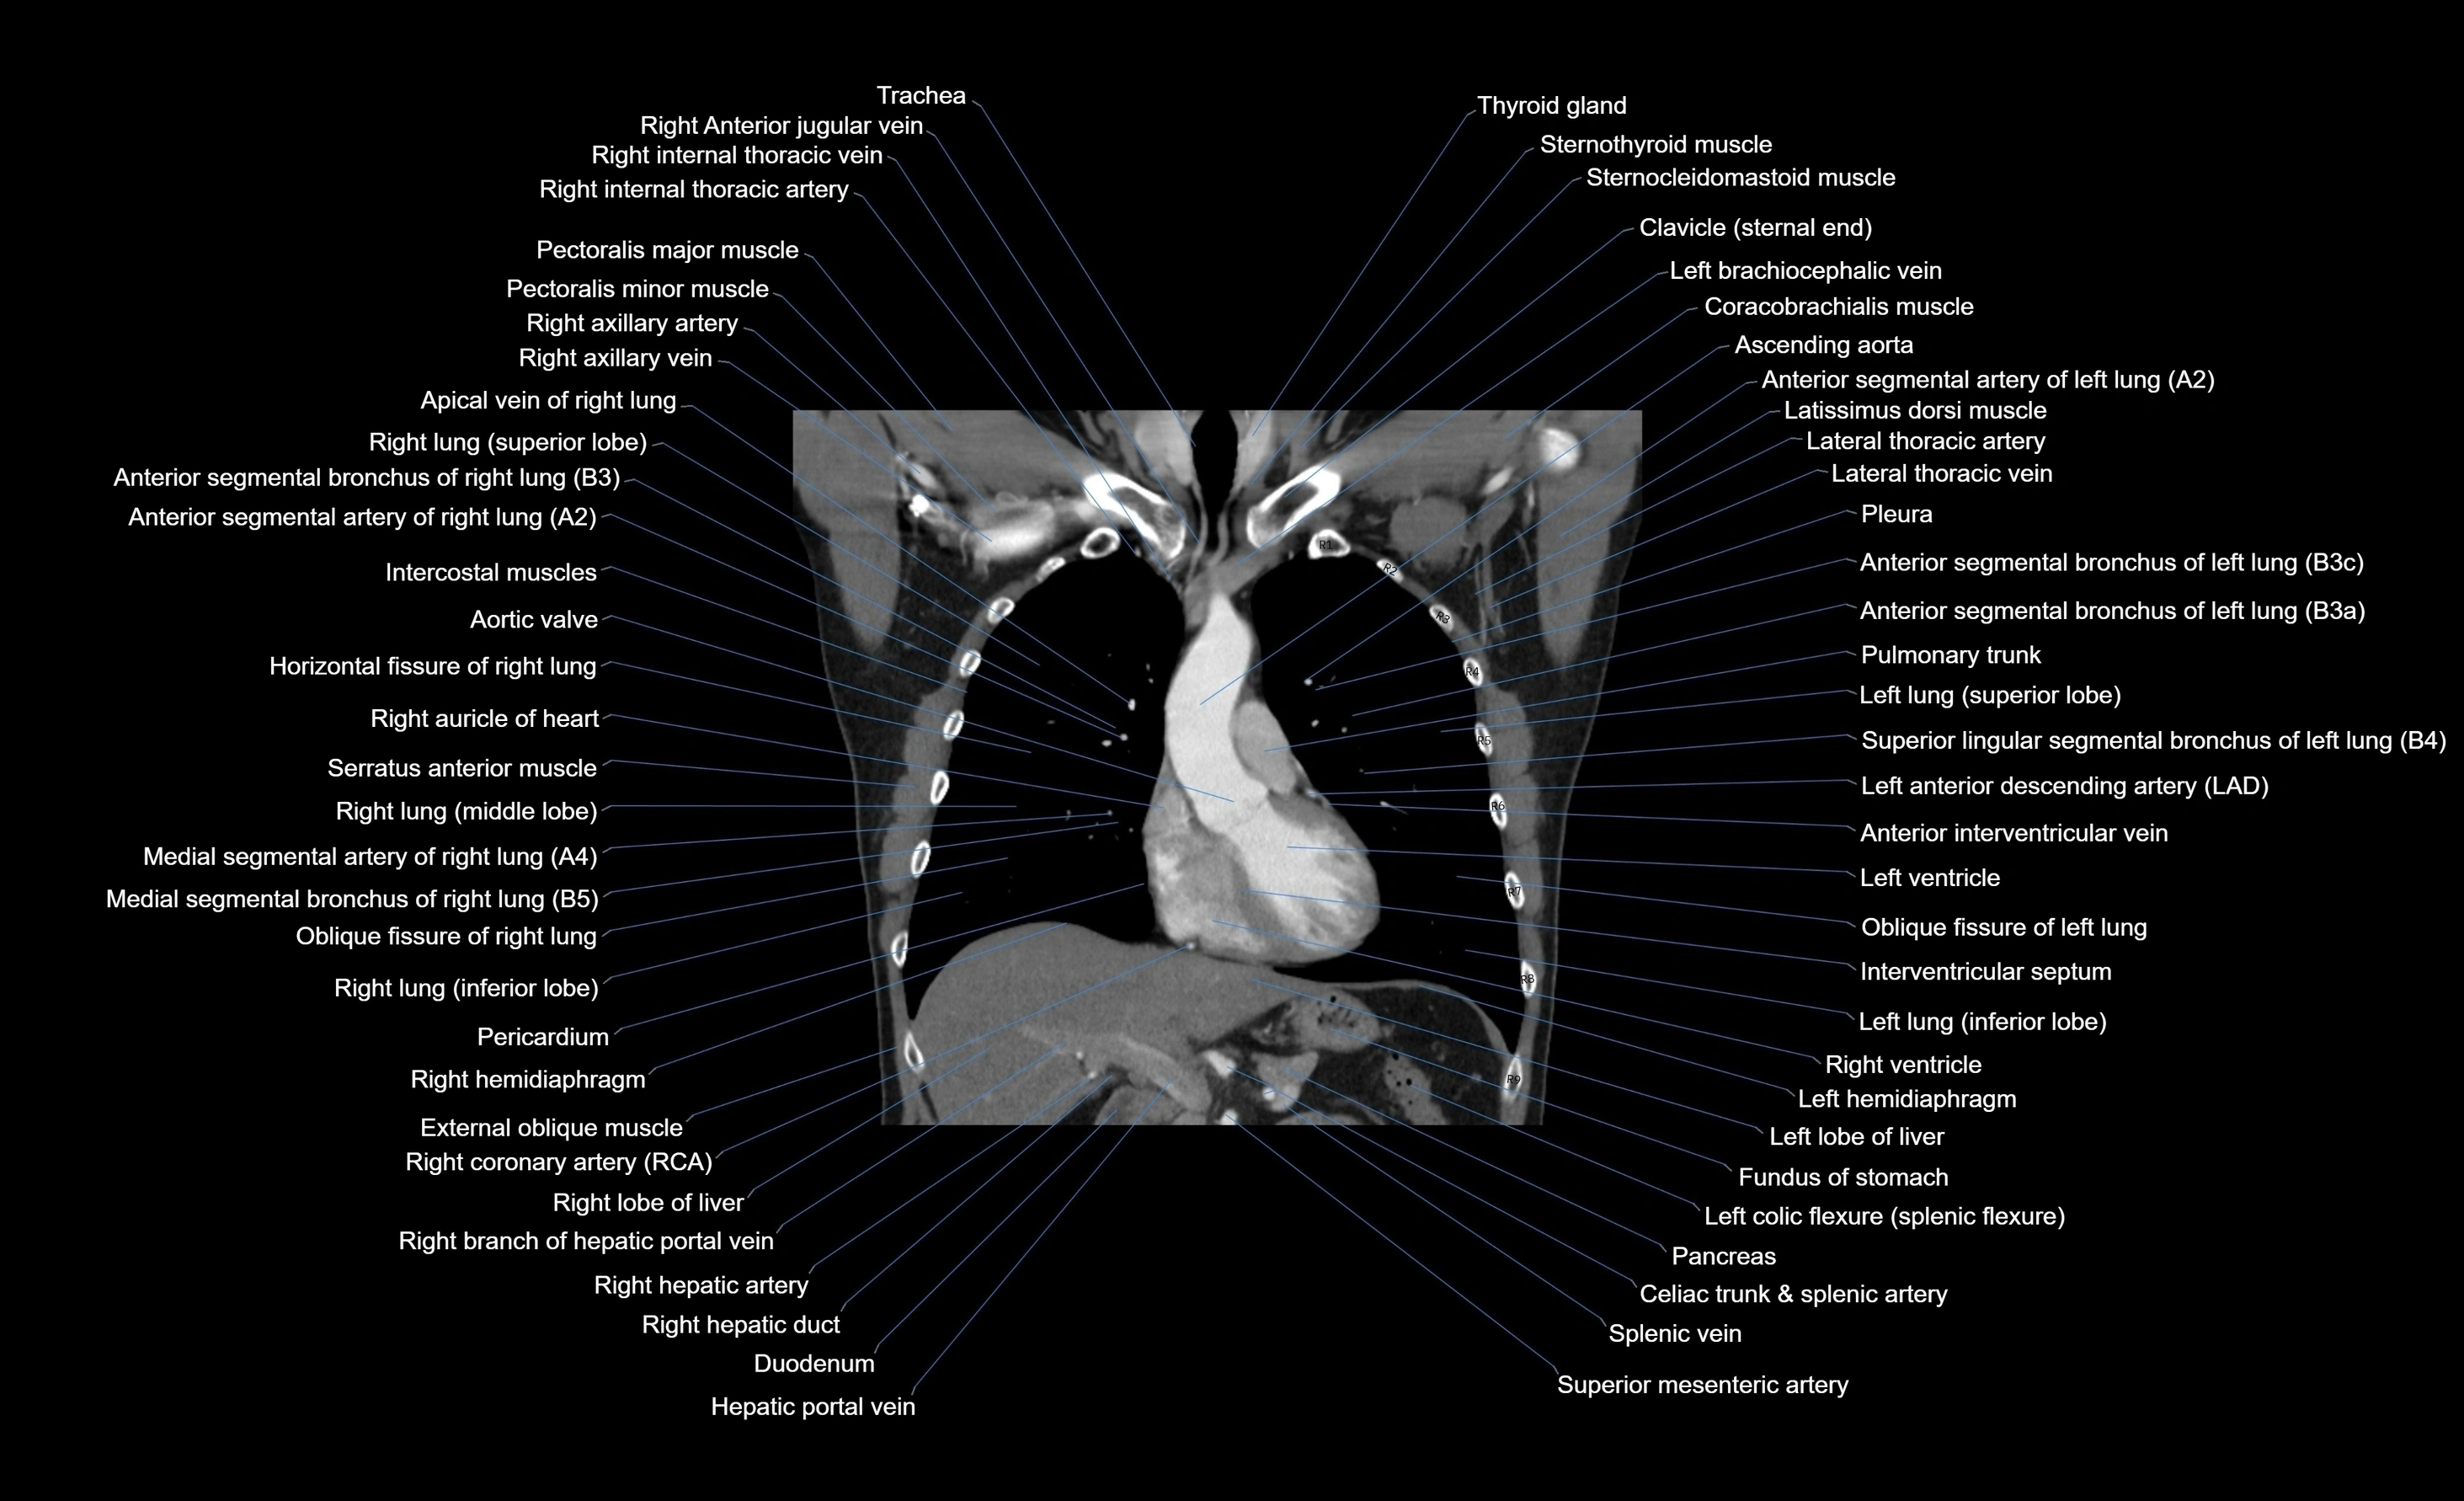

CT images